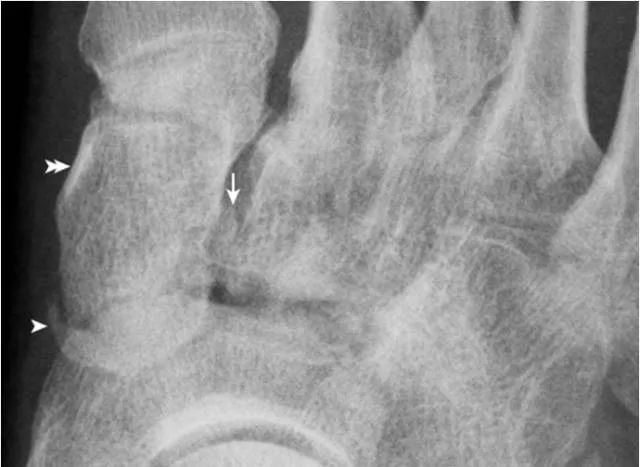

6.楔骨间骨:

为内侧及中间楔骨间副骨,边缘光滑(箭),属正常变异。内侧楔骨前内缘致密影(双箭头)为胫骨前肌肌腱附着处后缘的切线位投影,非病变。内侧楔骨与舟骨间见楔舟内侧骨(箭头)。